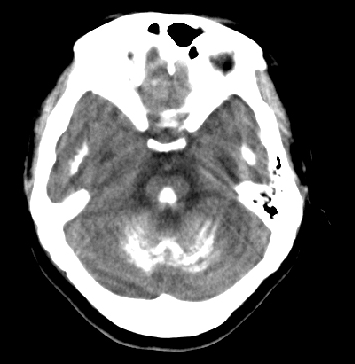

女性 38岁 病人脚弓反张 8岁以后不能行走 今年查pth11.9ng/ml(正常28ng/ml)

这么弥漫的钙化还第一次见。

考虑甲状旁腺功能减退症,该病是因甲状旁腺激素分泌减少或功能障碍所引起的少见病。其特点是低血钙,高血磷,且血pth极低。因低钙常可引起神经精神激惹症状,包括手指,趾,口角麻木,严重时可出现肌肉痉挛,喉哮鸣和惊厥,甚至癫痫样发作,有的可出现抑郁症及精神失常。长期的高磷血症可引起脑内结构对称性多发性钙化,特别是小脑和基底节的钙化可致锥体外系症状,而钙化的ct表现为类似于脑出血的密度增高影。

原发性甲状旁腺功能减退症和fahr病都有神志上的改变等症状,且头颅ct检查均可见颅内出现钙化。但fahr病无pth低下,ct表现钙化影在大脑半卵圆中心皮髓质交界处、丘脑、小脑齿状核等处。 而甲状旁腺功能减退症pth极低,ct虽可见钙化影,但部位在小脑和基底节等处。